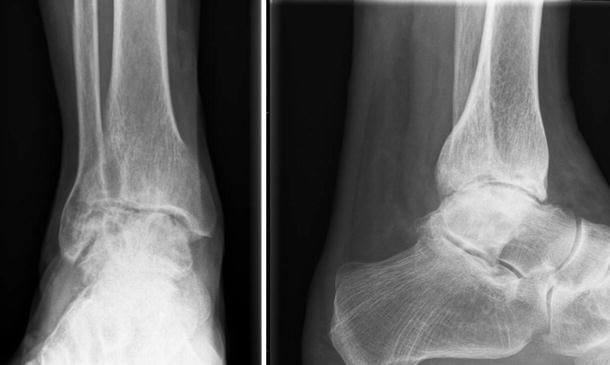

Artrodeza artroscopica de glezna este indicata in artroza avansata de glezna. Interventia ideala este cea care are sanse de succes de aproape 100% la prima incercare posibila (90-95% cazul fuziunii artroscopice a gleznei) și permite pacientului sa recupereze cat mai repede. De asemenea, ar trebui sa aiba un nivel scazut de durere postoperatorie.

Operatia se efectueaza utilizand standard doua incizii mici pentru artroscopia gleznei, precum si alte doua incizii mici pentru a plasa cele doua suruburi necesare pentru fixare (de obicei, in partea mediala a gleznei).

Interventia presupune efectuarea a doua incizii de cca 4mm in zona mediala si laterala a gleznei, si introducerea unei camere optice de 2.8 sau 4mm grosime pentru a se inspecta articulatia afectata. Cu ajutorul unui instrumentar special, se elimina tot cartilajul articular ramas si se regularizeaza suprafetele articulare, astfel incat contactul dintre cele 2 oase (tibie si talus) sa fie cat mai mare. Ulterior, se efectueaza inca 2 incizii de circa 5 mm in zona mediala a gleznei (sau una mediala si un laterala), si sub control radiologic se fixeaza articulatia afectata cu 2-3 suruburi de titan, de 5mm grosime, compactand (apropiind) cele 2 suprafete osoase.